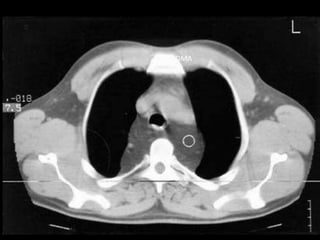

TOMOGRAFIA